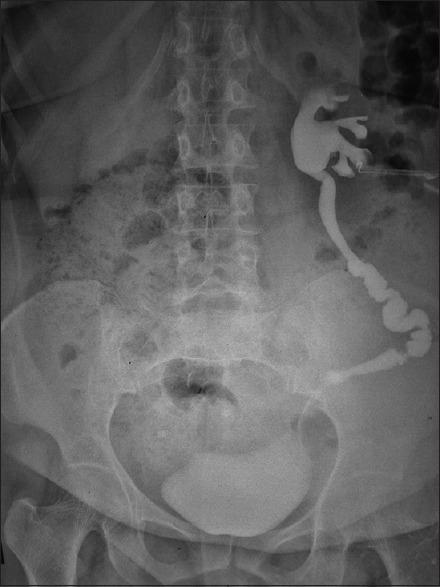

A total of 14 patients were studied. Two most common indications for performing ileal ureter were iatrogenic injury and radiation-induced strictures (5-5 cases). Most common site of ureteric involvement was lower and midureter seen in 6 cases. The mean length of the ileum used was 11.2 cm. Mean preoperative nadir creatinine level was 1.57 mg/dL in this study. Average postoperative creatinine level at 4-week follow-up was 1.75 mg/dL and 1.45 mg/dL and 1.37 mg/dL, at 3 and 12 months, respectively. The most common short-term complication was paralytic ileus and long-term complication was recurrent urinary tract infection UTI. There was no mortality.

共研究了14例患者。进行回肠代输尿管术的两个最常见指征是医源性损伤和放射性狭窄(各5例)。输尿管受累最常见的部位是输尿管中下段,共6例。所用回肠的平均长度为11.2厘米。本研究中患者术前肌酐水平最低点的平均值为1.57毫克/分升。术后4周随访时肌酐水平的平均值为1.75毫克/分升,3个月和12个月时分别为1.45毫克/分升和1.37毫克/分升。最常见的短期并发症是麻痹性肠梗阻,长期并发症是复发性尿路感染。无死亡病例。